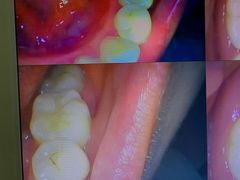

• 土豆口腔(凤凰北总店)

• -土豆口腔(凤凰北总店)

匿名用户 | 22-11-06